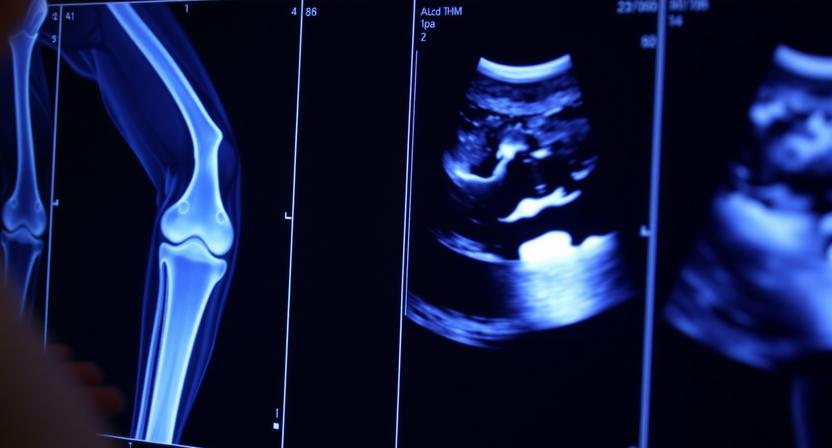

سونار الركبة المنزلي بدون انتظار: احجز الآن بسهولة السونار المنزلي

سونار الركبة المنزلي بدون انتظار: احجز الآن بسهولة

آلام الركبة من أكثر المشكلات شيوعًا، سواء بسبب إصابة رياضية أو إجهاد يومي. الحل لم يعد يتطلب الذهاب لمركز أشعة... اقرأ المزيد